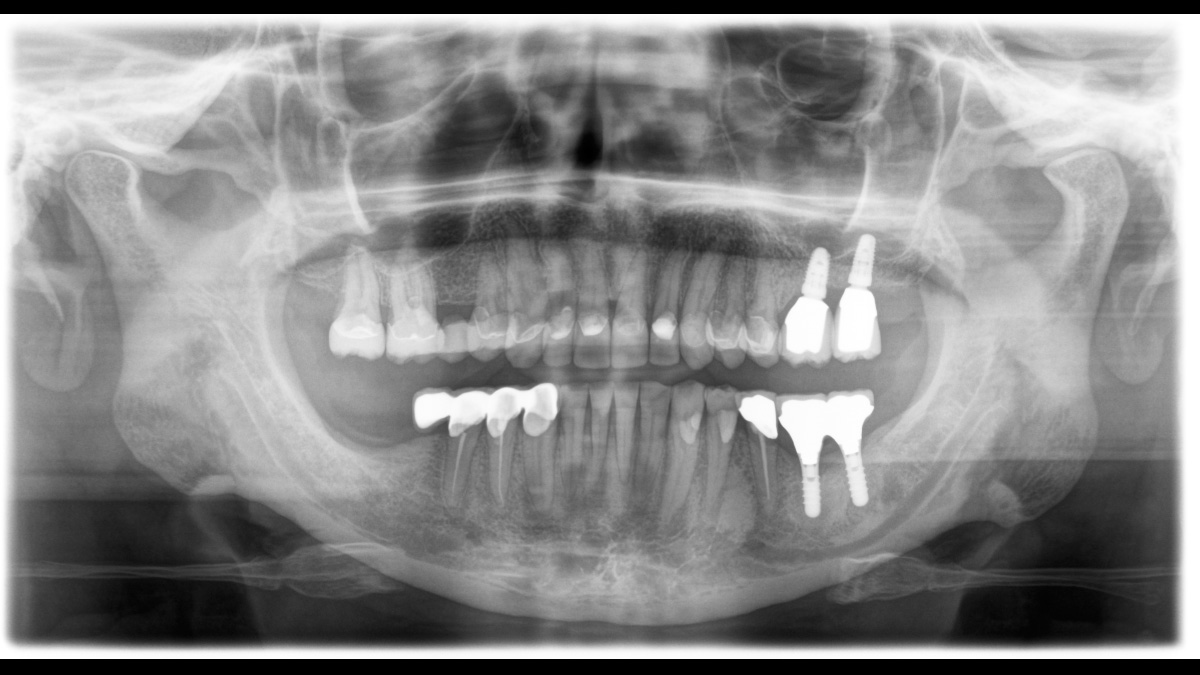

Für hervorragende Panorama-Röntgenaufnahmen ist der richtige Fokus entscheidend. Mit der Autofokusfunktion erhalten Sie automatisch ein Bild mit der bestmöglichen Schärfe im Fokus. Dentsply Sirona Röntgengeräte erstellen in einem Umlauf mehrere tausend Einzelaufnahmen und erkennen vollautomatisch die Bereiche, in denen der Kiefer optimal in der scharfen Schicht liegt. Ohne zusätzliche manuelle Schritte werden diese Bilder dann in einem Gesamtbild mit maximaler Zeichenschärfe dargestellt.

Einige Teile des Bildes sind scharf, andere Bereiche bleiben unscharf.

Das System erkennt in einem Umlauf die relevanten Bereiche aus mehreren tausend Einzelbildern und identifiziert automatisch die Bereiche, in denen der Kiefer optimal in der scharfen Schicht liegt.

Zeichenscharfe Bilder.